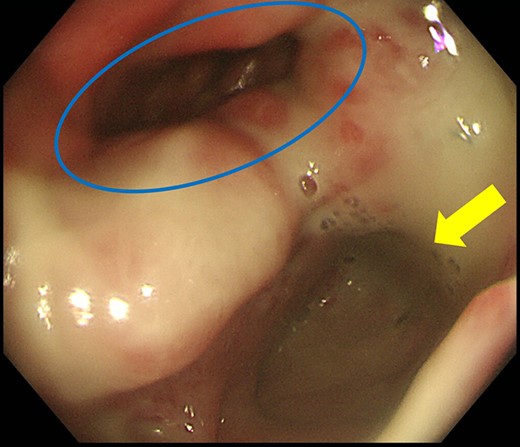

Case 1 was a 71-year-old man with a BMI of 29.7 kg/m2. Laparoscopic low anterior resection (LAR) and ileostomy was performed for rectal cancer in 2017 years. Postoperative fever and lower abdominal pain were noted, and colonoscopy was performed, and anastomotic leakage was noted with a correction of about 1/2 around the 6 o’clock direction of the anastomotic region, and fistula and formation of a large abscess cavity. After identification (Fig. 1), a tube was inserted for drainage and conservative treatment was performed. The patient was discharged on POD 46. Four months after the operation, marked improvement in the abscess cavity was noted but still remained (Fig. 2a and b). Anastomotic leakage was almost improved by colonoscopy at 17 months after surgery, but at the preference of the patient we performed colostomy 22 months after surgery (Fig. 3). It took a long time to improve intestinal movement of the colon because the large intestinal tract had not been used for a long time, and conservative treatment was performed using a nasogastric tube for paralytic ileus. Diet was initiated 7 days after surgery, and the patient was discharged from the hospital 14 days after surgery. The Wexner score [2] was 19 points one month after closure, 17 points 3 months after the operation and 16 points after 6 months after the operation, and severe anal dysfunction was observed, but gradually improved.

Colonoscopy revealed a true lumen (circle), an anastomotic site (triangle) and a cavity due to suture failure (arrow).